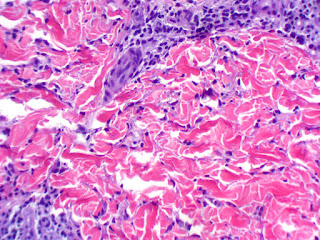

Pathology: There is a superficial and mid-perivascular and interstitial lymphocytic infiltrate with neutrophils and rare eosinophils. (Photomicrographs courtesy of Dr. Marjan Mirzabeigi, Dermatopathology, Boston University Department of Dermatology)

Diagnosis: Clinically, I considered a viral exanthem or the urticarial phase of Henoch-Schoenlein Purpura. Histologically, the suggestions were interstitial granulomatous dermatitis (IGD) or an interstitial variant of granuloma granuloma annulare.